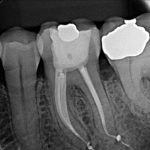

No artigo a seguir vamos mostrar o caso de um molar inferior com cinco canais. Dentre eles, o canal mésio-medial – localizado entre o mésio-vestibular e o mésio-lingual – e que está presente entre 1 e 15% dos casos.

A paciente foi encaminhada já com o acesso realizado no dente 36, após o diagnóstico de pulpite aguda irreversível. Após a anestesia, isolamento do campo operatório e remoção da restauração provisória, foram encontrados cinco canais com auxílio da microscopia. Entre eles, o canal mésio-medial, na raíz mesial, e situado entre o canal mésio-vestibular e o mésio-lingual.

A obturação foi realizada com a técnica do cone único com cimento AH Plus. O selamento da cavidade de acesso foi feito em resina composta e o paciente encaminhado para o protesista.